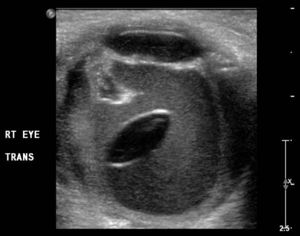

- Ultrasound

- Lense displaced from usual position

- evidence of other associated traumatic injuries